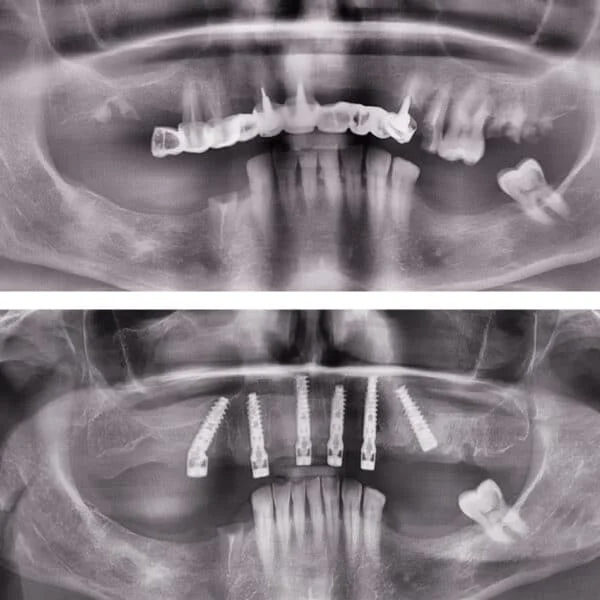

Implantul dentar este adesea recomandat deoarece prezintă foarte multe avantaje, iar, de multe ori, este unica soluție pentru protezarea unei edentații.